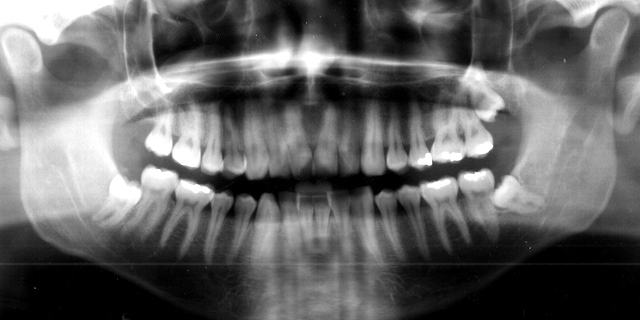

Radiografia Panoramica , com 7 dentes do Sisos!